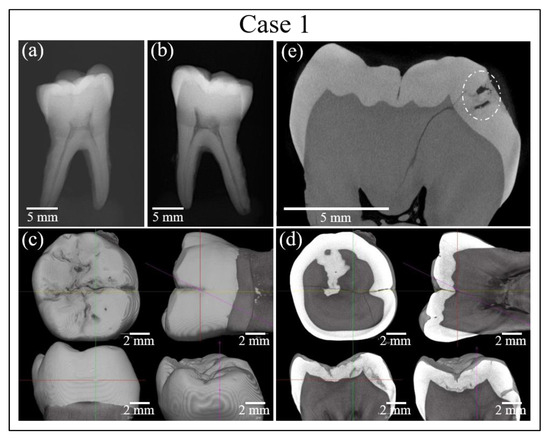

Figure 2 and Figure 3 show the results of additional analyses of the sample in Case 1. Figure 2a shows a digital microscopic image of the discolored area in the tooth sample, while Figure 2b–d show the location of the cavity as assessed by micro-CT and reconstructed into a 3D image. Figure 3a,b show the results of conventional X-ray analyses, while Figure 3c–e show high-resolution micro-CT scanning examinations. However, analyses by conventional methods gave no clear indication regarding the possible presence of buried caries, which remained hardly detectable by digital microscopy (cf. red circles in inset to Figure 2b–d) and completely invisible in conventional X-ray radiographs (cf. Figure 3a,b). Conversely, high-resolution CT-scanning clearly detected the presence of sub-surface caries (cf. encircled region in Figure 3e). It should be noted, however, that, due to radiation-related safety issues, in-vivo micro-CT imaging exams are usually performed only when there is a clear medical benefit. This method is therefore not a common choice for routine caries detection.

Figure 3.

(a,b) Results of conventional X-ray analyses of the tooth sample in Case 1. (c–e) High-resolution micro-CT scanning examinations of the same sample. Dotted circle indicates cavity.